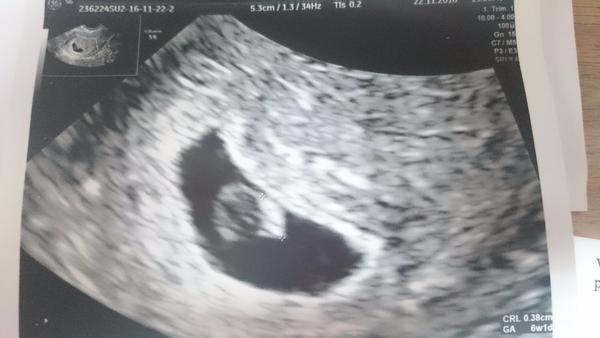

Ahoj, jsem tady nová. Nejsem ještě zkušená s těmihle věcmi ale myslím si, že by to mohlo být pozitivní? viz foto předtím.. Mohu poprosit o vaše rady ? a zkušenosti ?

@baskooskavy Chápu, že je to dlouhý, ale doktor by tam stejně nic neviděl 🙂 Pak už bude určitě i srdíčko 🙂 Veřte miminku, že se udrží a ono to zvládne, nervování tomu nepomůže 🙂

@irenka84 jeee tak tj super že jste v pořádku!! 🙂 gratuluji a držím palečky do dalších týdnu..a co byste víc chtěli? Chlapečka či holčičku? Já byla dnes na kontrole na srdicko a je to fakt nadherne jak to tluče... Až dnes jsem tomu opravdu nějak uvěřila... 🙂 další kontrola az za 4 týdny, to bude věčnost! :D